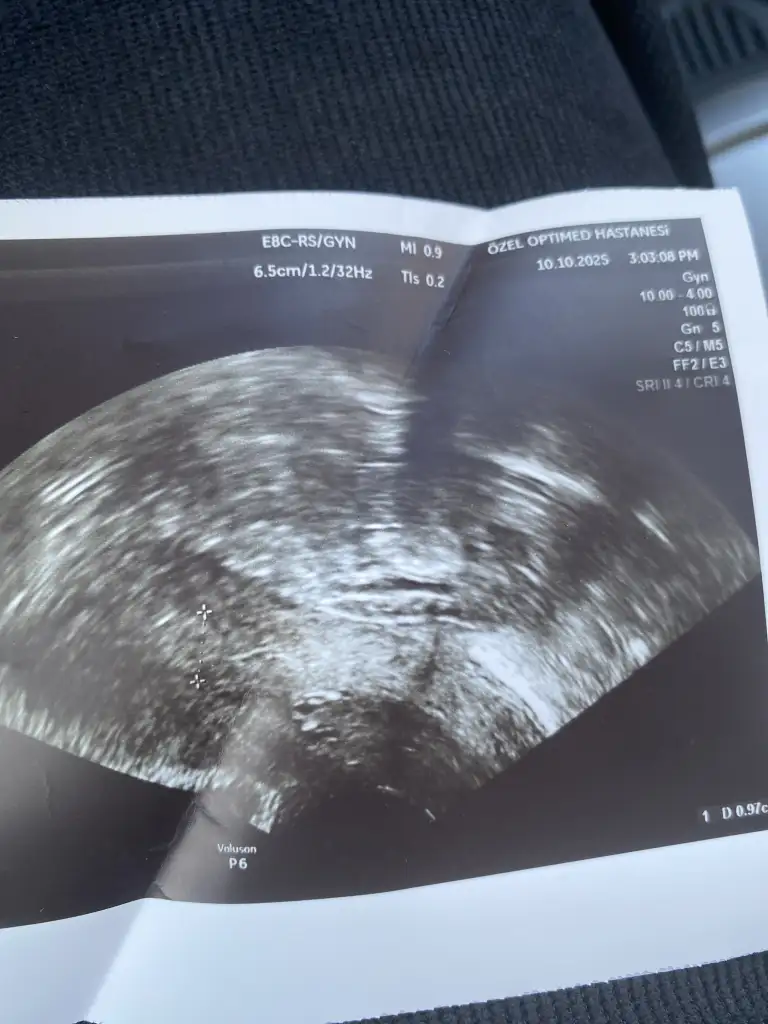

Kızlar doktor gebelikten şüphelendi rahim duvar kalın dedi kan testi negatif çıktı adet oldum yeni sizce gebelik kesesi mi görünen. Sağlık sorunum var ağır ilaçlar kullanıyorum kan değerini ilaçlar etkilemiş olabilir mi benzer durum yaşayan var mı